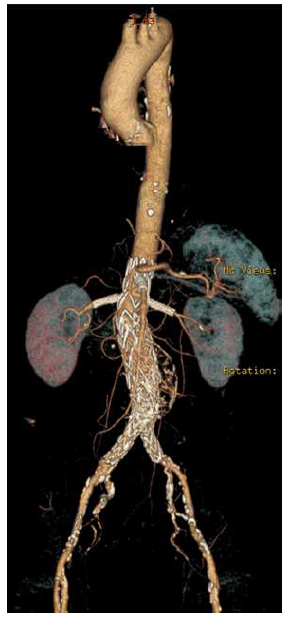

The patient was discharged home on the ninth postoperative day. A six-month follow-up CTA confirmed the AAA's exclusion, with maintained patency of all visceral vessels and no evidence of endoleak (Figure 3). No further clinical events were related to the AAA or the PMEG.

Complete exclusion of the juxta-renal aneurysm is noted, with no evidence of endoleak, and patency of all target visceral vessels is maintained.